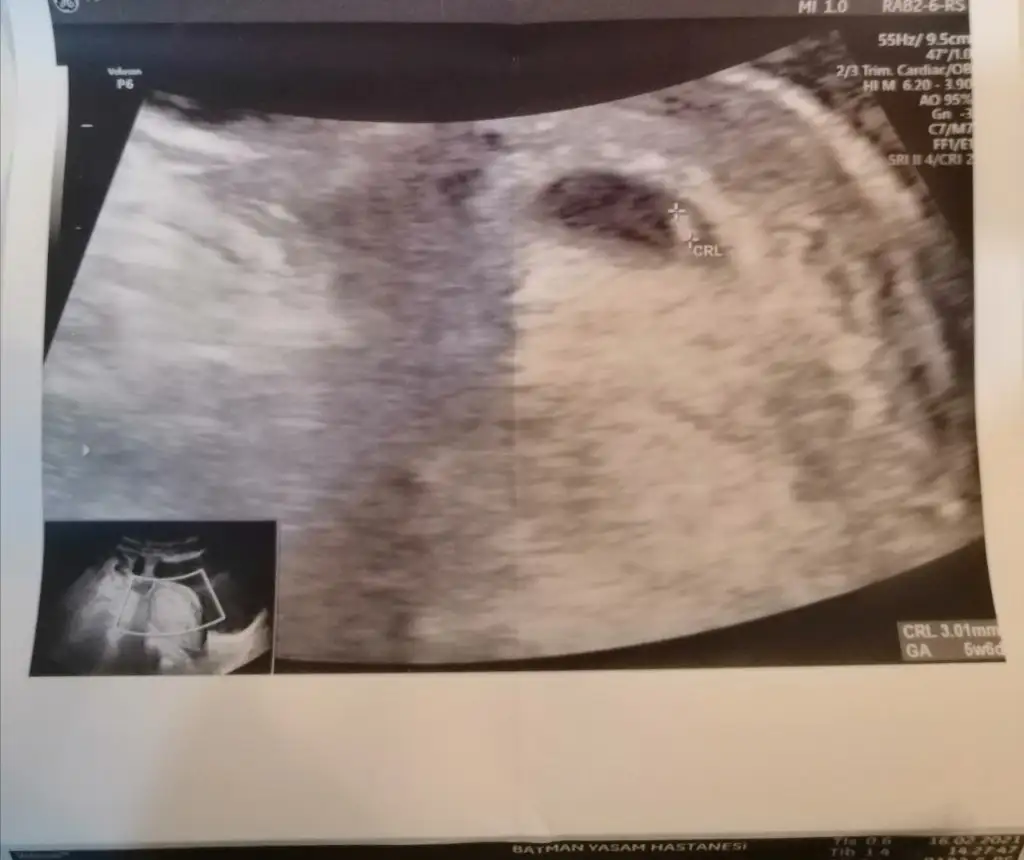

Doktor 5+6 dedi ama ben biliyorumki 16 Ocakta oldu. Benim hesabıma göre 4+3. İlk haftadan gebelik belirtileri gördüm vallahi. Özellikle kokuda hassasiyet, alt karın ve kasık ağrısı halsizlik yorgunluk mide bulantısı hemen başladı. Sürekli midem bulanıyor başımı kaldıramıyorum.

Hayırlı olsun canım rabbim gönlündekini nasip etsin 🥰 hamilelik haftasında SAT tarihi baz alınır ilişki günü değil yani doktorun dediği 5+6 doğru hiç boşuna aklını karıştırma 🙏 çok şükür kalp atışını da duymuşsun darısı bana 😇